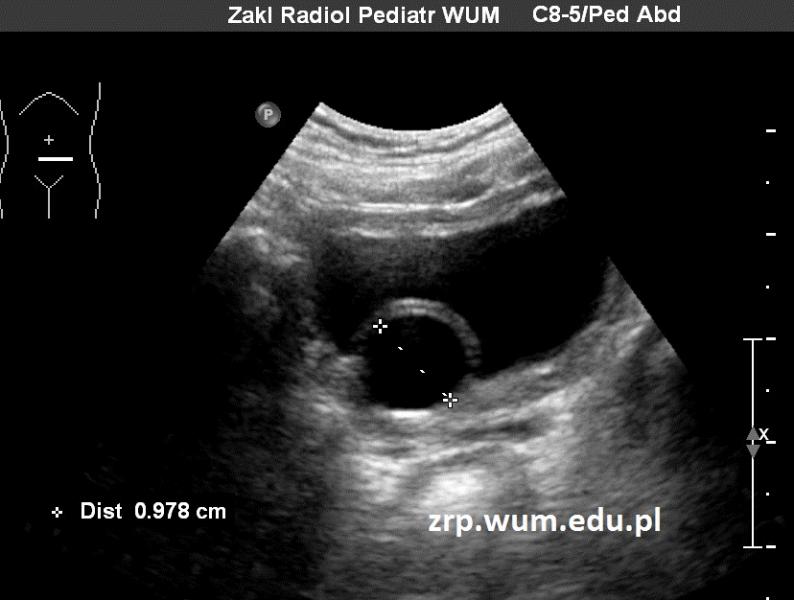

Przypadek 55: 16-letni chłopiec z podejrzeniem guza śródpiersia górnego, wykrytego w kontrolnym badaniu echokardiograficznym.

Rozpoznanie: Na zdjęciu RTG klatki piersiowej stwierdzono poszerzenie cienia śródpiersia po stronie lewej, w rzucie lewej wnęki. W trakcie dalszej diagnostyki rozpoznano chłoniaka.